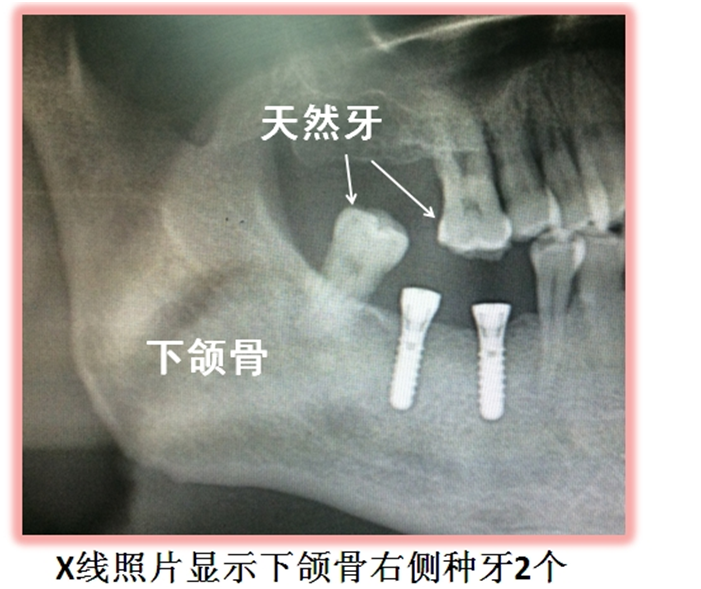

種植牙之前,一般是需要先拍全景片的,不僅(jin) 可以看到全部的牙齒,而且每個(ge) 牙齒的情況都是可以看到的,比如說是否有殘根,要不要拔牙?有沒有智齒等。然後醫生才能結合其他情況製定合適的種植牙方案。 種植牙拍片需要根據牙齒情況來確定要做哪些檢查,不止是需...

種植牙之前,一般是需要先拍全景片的,不僅(jin) 可以看到全部的牙齒,而且每個(ge) 牙齒的情況都是可以看到的,比如說是否有殘根,要不要拔牙?有沒有智齒等。然後醫生才能結合其他情況製定合適的種植牙方案。

種植牙拍片需要根據牙齒情況來確定要做哪些檢查,不止是需要做全景片,可能還需要對蛀牙嚴(yan) 重的牙齒做小牙片檢查,以及要更好的查看牙齒排列以及頜骨異常等情況,可能需要拍側(ce) 位片以及ct片等。